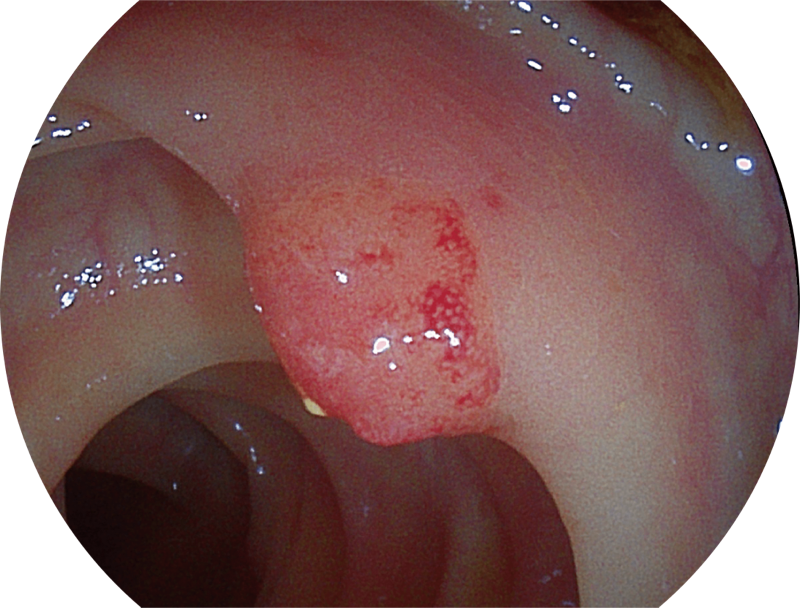

SFI图像

能够凸显黏膜浅层血管轮廓和黏膜表面微结构,适用于中、近景观察下的早癌精确诊断。